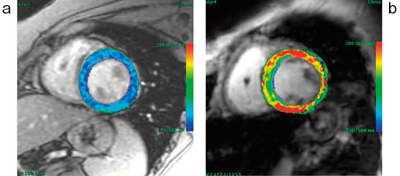

また,T2*マップ解析では,マルチエコーのSegmented FGRE法を用いた撮像アプリケーション(StarMap)で得られたデータから,T2*減衰の差をカラーマッピング(R2*/T2*マップ)することが可能で,ROIを設定することでR2*やT2*の数値が表示される。これにより,心筋における鉄沈着を間接的に評価することが可能(図7)で,ヘモクロマトーシスやサラセミア等の疾患で臨床応用が期待されている。

図7 T2*マップ解析

a:正常心筋

b:鉄沈着の症例(赤い領域はT2*が短縮している)